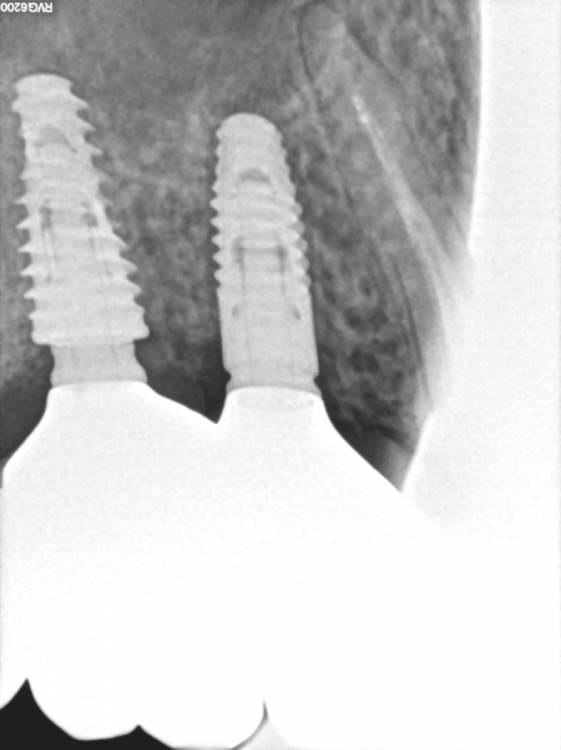

TIGER Опубликовано 22 сентября, 2022 Поделиться Опубликовано 22 сентября, 2022 (изменено) https://youtu.be/Flx36Opddh полное видео операции тут☝? Рутинный кейс)Закрытый синус,как всегда в скоп и при помощи пьезотома ,последнее фото результат через 6 месецев перед фиксацией протетики? Изменено 22 сентября, 2022 пользователем TIGER 5 1 Ссылка на комментарий

TIGER Опубликовано 7 октября, 2022 Автор Поделиться Опубликовано 7 октября, 2022 Финал 1 Ссылка на комментарий